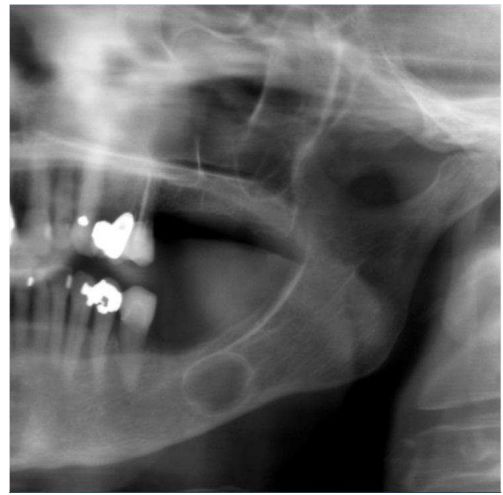

65.46歲女性因上顎左側犬齒牙根尖區域至鼻翼處腫脹來求診,經X光檢查如附圖1 所示,犬齒牙髓活性測試有活性反應,病患接受進一步影像檢查如附圖2 ,圖2影像之拍攝方式為下列何者? (A)電腦斷層掃描(computerized tomography) (B) 骨掃描(bone scan) (C)磁共振造影(magnetic resonance imaging) (D)超音波掃描(ultrasongraphy)